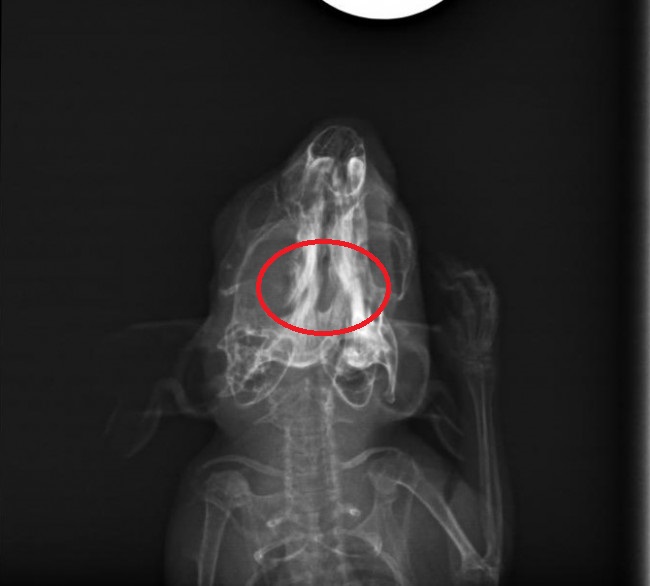

Die Röntgenbilder waren auch sehr Interessant anzusehen. Leider sieht man auf der seitlichen Aufnahme nicht sonderlich viel von dem Bruch, da sich der Knochen scheinbar nicht nach oben/unten verschoben hat.

Auf der anderen Aufnahme sah es für mich allerdings so aus, dass sich der Knochen auch ein Stück zur Seite verschoben hat. Die Bruchstelle hab ich mal eingekreist und für mich sieht es so aus, als ob die rechte und linke Hälfte des Kiefers betroffen sind.

@Viktor.K laut TA war / ist es auch ein doppelter Kieferbruch, deine Einkreisung könnte also stimmen